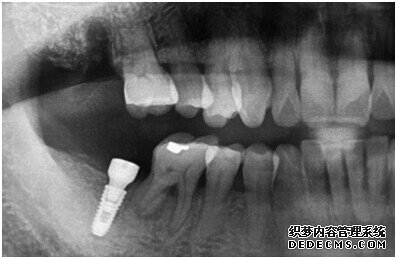

由CT片检查来看,刘女士口腔健康环境还是很好的,牙槽骨也适合种植牙的条件,而且由我们最后一颗牙是非常重要的,经过专家的建议和详细解释了原因之后,刘女士选择了美国百康种植牙。

成功植入种植体后的效果图

种植体成功植入后的CT效果图